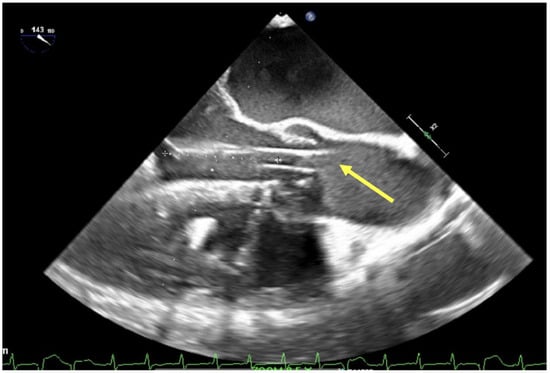

3.2. Dual-Lumen Considerations

| Assessment of peripheral vasculature for size, disease, thrombus | Assessment of return (outflow) “jet” | Confirmation of cannula position |

| Evaluation for pericardial fluid | Guidance for cannula repositioning | |